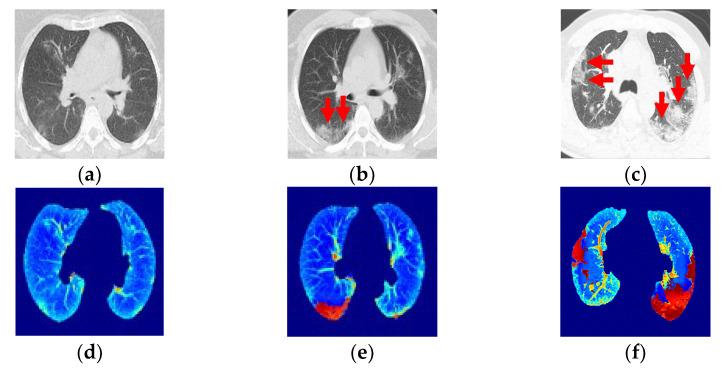

This app project was aimed to remotely deliver diagnoses and disease-progression information to COVID-19 patients to help minimize risk during this and future pandemics. Data collected from chest computed tomography (CT) scans of COVID-19-infected patients were shared through the app. In this article, we focused on image preprocessing techniques to identify and highlight areas with ground glass opacity (GGO) and pulmonary infiltrates (PIs) in CT image sequences of COVID-19 cases. Convolutional neural networks (CNNs) were used to classify the disease progression of pneumonia. Each GGO and PI pattern was highlighted with saliency map fusion, and the resulting map was used to train and test a CNN classification scheme with three classes. In addition to patients, this information was shared between the respiratory triage/radiologist and the COVID-19 multidisciplinary teams with the application so that the severity of the disease could be understood through CT and medical diagnosis. The three-class, disease-level COVID-19 classification results exhibited a macro-precision of more than 94.89% in a two-fold cross-validation. Both the segmentation and classification results were comparable to those made by a medical specialist.

这个应用程序项目旨在通过远程为 COVID-19 患者提供诊断和疾病进展信息,以帮助在此次和未来的大流行期间降低风险。通过该应用程序共享从 COVID-19 感染患者的胸部计算机断层扫描(CT)扫描中收集的数据。在本文中,我们专注于图像预处理技术,以识别和突出 COVID-19 病例的 CT 图像序列中存在磨玻璃影(GGO)和肺部浸润(PI)的区域。使用卷积神经网络(CNN)对肺炎的疾病进展进行分类。使用显著图融合突出显示每个 GGO 和 PI 模式,并使用所得图谱训练和测试具有三个类别的 CNN 分类方案。除了患者,该信息还通过应用程序在呼吸分诊/放射科医生和 COVID-19 多学科团队之间共享,以便通过 CT 和医学诊断了解疾病的严重程度。在两轮交叉验证中,COVID-19 三级疾病分类结果的宏观精度超过 94.89%。分割和分类结果与医学专家的结果相当。